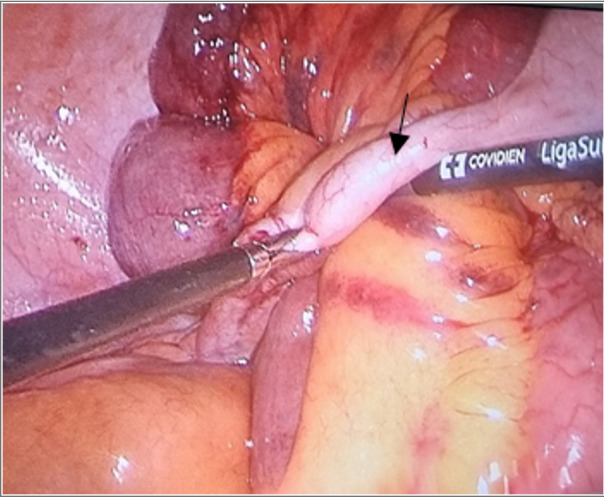

Sleeve gastrectomy is a popular surgical procedure for weight loss. Although it is basically a safe surgery; however, it can lead to serious complications such as intestinal obstruction. The present report describes a 55-year-old woman who attended with complications of abdominal pain and vomiting that underwent laparoscopic exploratory intervention and ileum obstruction due to adherent bands of the appendix was considered as final diagnosis.